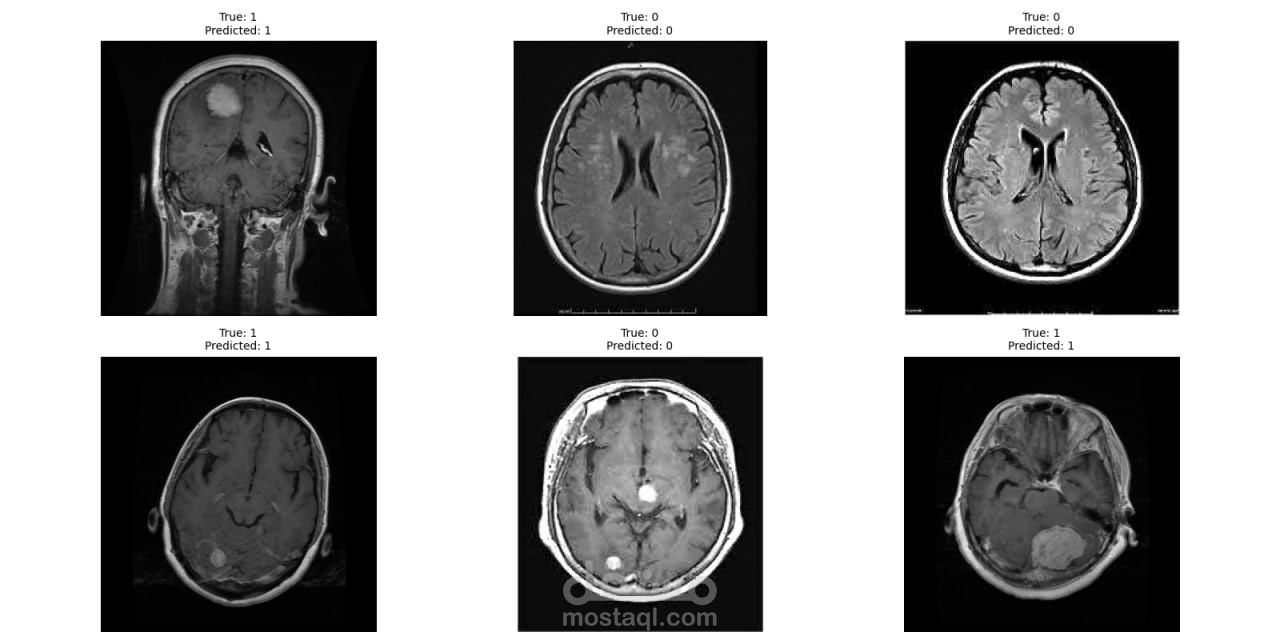

المشروع يهدف إلى تطوير نظام ذكي لتصنيف أورام الدماغ باستخدام تقنيات التعلم العميق، مع التركيز على نموذج VGG16 الذي يُعد من أبرز النماذج الفعالة في هذا المجال. يسعى المشروع إلى تمكين الأطباء والباحثين من تحليل الصور الطبية بدقة وكفاءة.

- الاعتماد على تقنيات متقدمة: استخدام نموذج VGG16 المعروف بأدائه المتميز في تحليل الصور.

- دقة عالية في التصنيف: توفير نتائج دقيقة لدعم القرارات الطبية.

يهدف هذا المشروع إلى تعزيز المجال الطبي من خلال أتمتة وتحسين عمليات التشخيص، مما يساهم في تسريع الإجراءات الطبية وإنقاذ الأرواح. أرحب بمناقشة أي تفاصيل إضافية أو تخصيص النظام وفقاً لمتطلبات معينة.